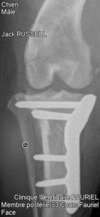

Radiographie

Des radiographies des membres, des articulations, du crâne ou de la colonne peuvent être réalisées, en particulier dans le cadre des consultations orthopédiques ou de traumatologie.